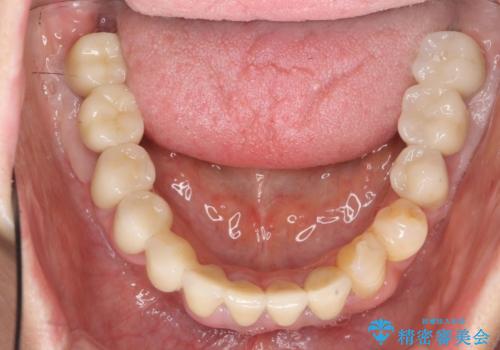

歯周病 全顎治療

- 前歯の見た目、入れ歯による噛めないことの改善を求めて来院されました。

検査により全顎的な歯周病治療、欠損のインプラント補綴、根管治療が必要な状態であることをお伝えし、治療を計画します。

失ってしまった機能を回復し、今後歯を失わないよう残せる歯に歯周病治療を行い、安定した咬合を確立することで長期的に問題なく噛めるような口腔内環境を達成できるようになると考えます。